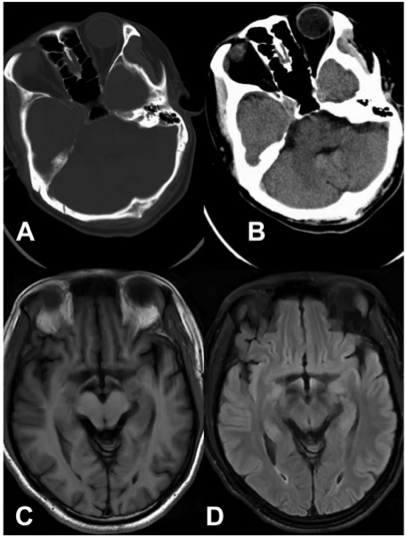

第九次ECT治疗后,患者出现谵妄,出现时间和位置迷失、短时记忆力下降、表情迟钝和缓慢、嗜睡、听觉和视觉幻觉。谵妄诊断评分为29。患者的血Li浓度为1.21 mmol/L。ECT停止,Li剂量降至500mg/d。ECT期间,血压在102~155/67~108 mmHg之间波动。五天后,患者意识恢复,但出现失语症(单词选择失败)。但他对书面和口语的理解没有改变,而且他能准确地书写和阅读。脑CT显示无出血或缺血(图1 A和B)。患者在出现失语症3天后还接受了头部磁共振成像(MRI),未发现异常(图1 C和D)。一周内,失语症消失,情绪稳定。随后,患者服用Li 750 mg/d和奎硫平200 mg/d。一个月后,在他的第一次回顾访问中,患者头脑清晰,方向完整,并且能够正确地命名物体。患者主诉情绪一直很稳定。杨氏躁狂评定量表评分为5分,汉密尔顿抑郁评定量表-17评分为6分,阳性和阴性症状量表评分为40分。

图1. A和B显示患者的头部计算机断层扫描图像;C和D显示患者的头部磁共振成像扫描图像